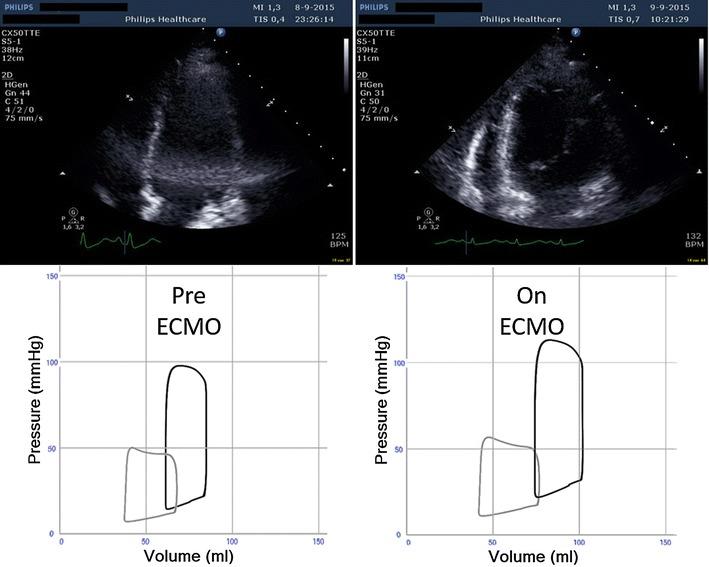

用于在静脉-动脉体外膜肺氧合期间监测心脏负荷的个体化实时临床决策支持。

Individualized real-time clinical decision support to monitor cardiac loading during venoarterial ECMO.

Veno-arterial extracoporeal membrane oxygenation (VA ECMO) is increasingly used for acute and refractory cardiogenic shock. Yet, in clinical practice, monitoring of cardiac loading conditions during VA ECMO can be cumbersome. To this end, we illustrate the validity and clinical applicability of a real-time cardiovascular computer simulation, which allows to integrate hemodynamics, cardiac dimensions and the corresponding degree of VA ECMO support and ventricular loading in individual patients over time.

静脉-动脉体外膜肺氧合(VA ECMO)越来越多地用于急性和难治性心源性休克。然而,在临床实践中,VA ECMO期间心脏负荷状况的监测可能很麻烦。为此,我们阐述了一种实时心血管计算机模拟的有效性和临床适用性,该模拟能够随时间整合个体患者的血流动力学、心脏大小以及VA ECMO支持和心室负荷的相应程度。